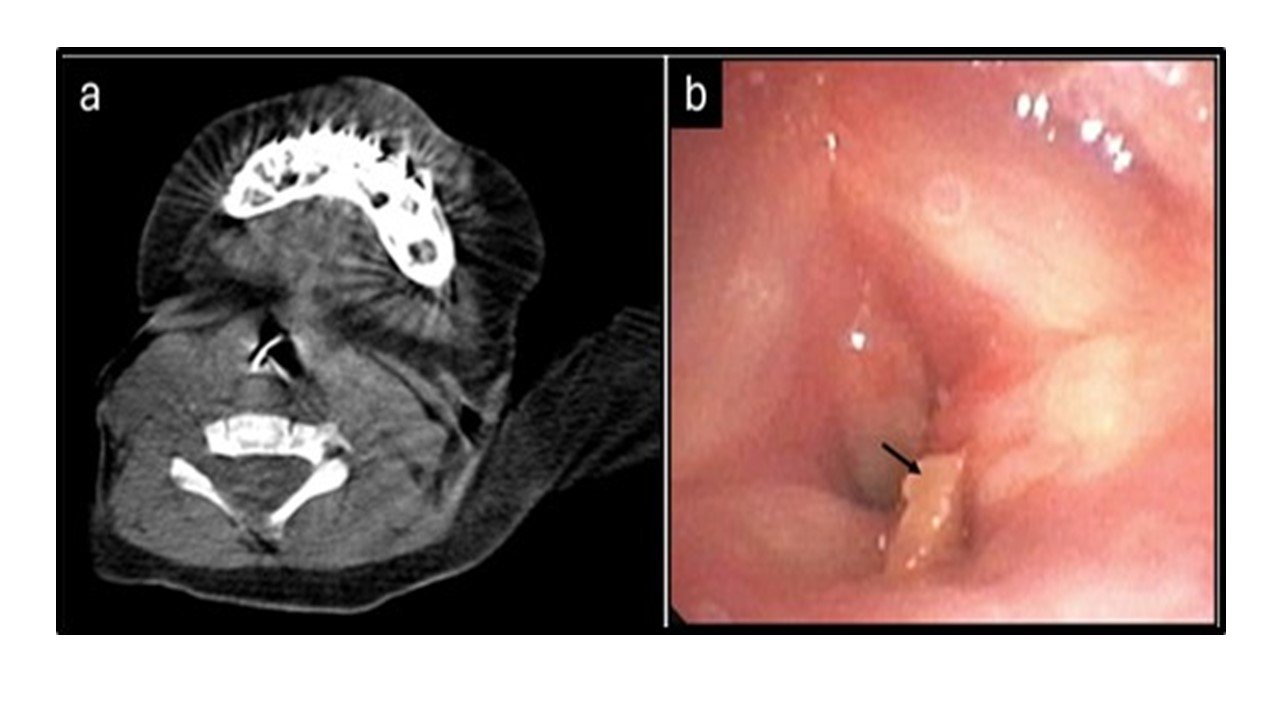

Methods: We report a case of airway obstruction caused by an aspirated chicken bone in an 11-month-old infant. The FB was successfully extracted with the use of extracorporeal membrane oxygenation (ECMO) to maintain oxygenation during the procedure.